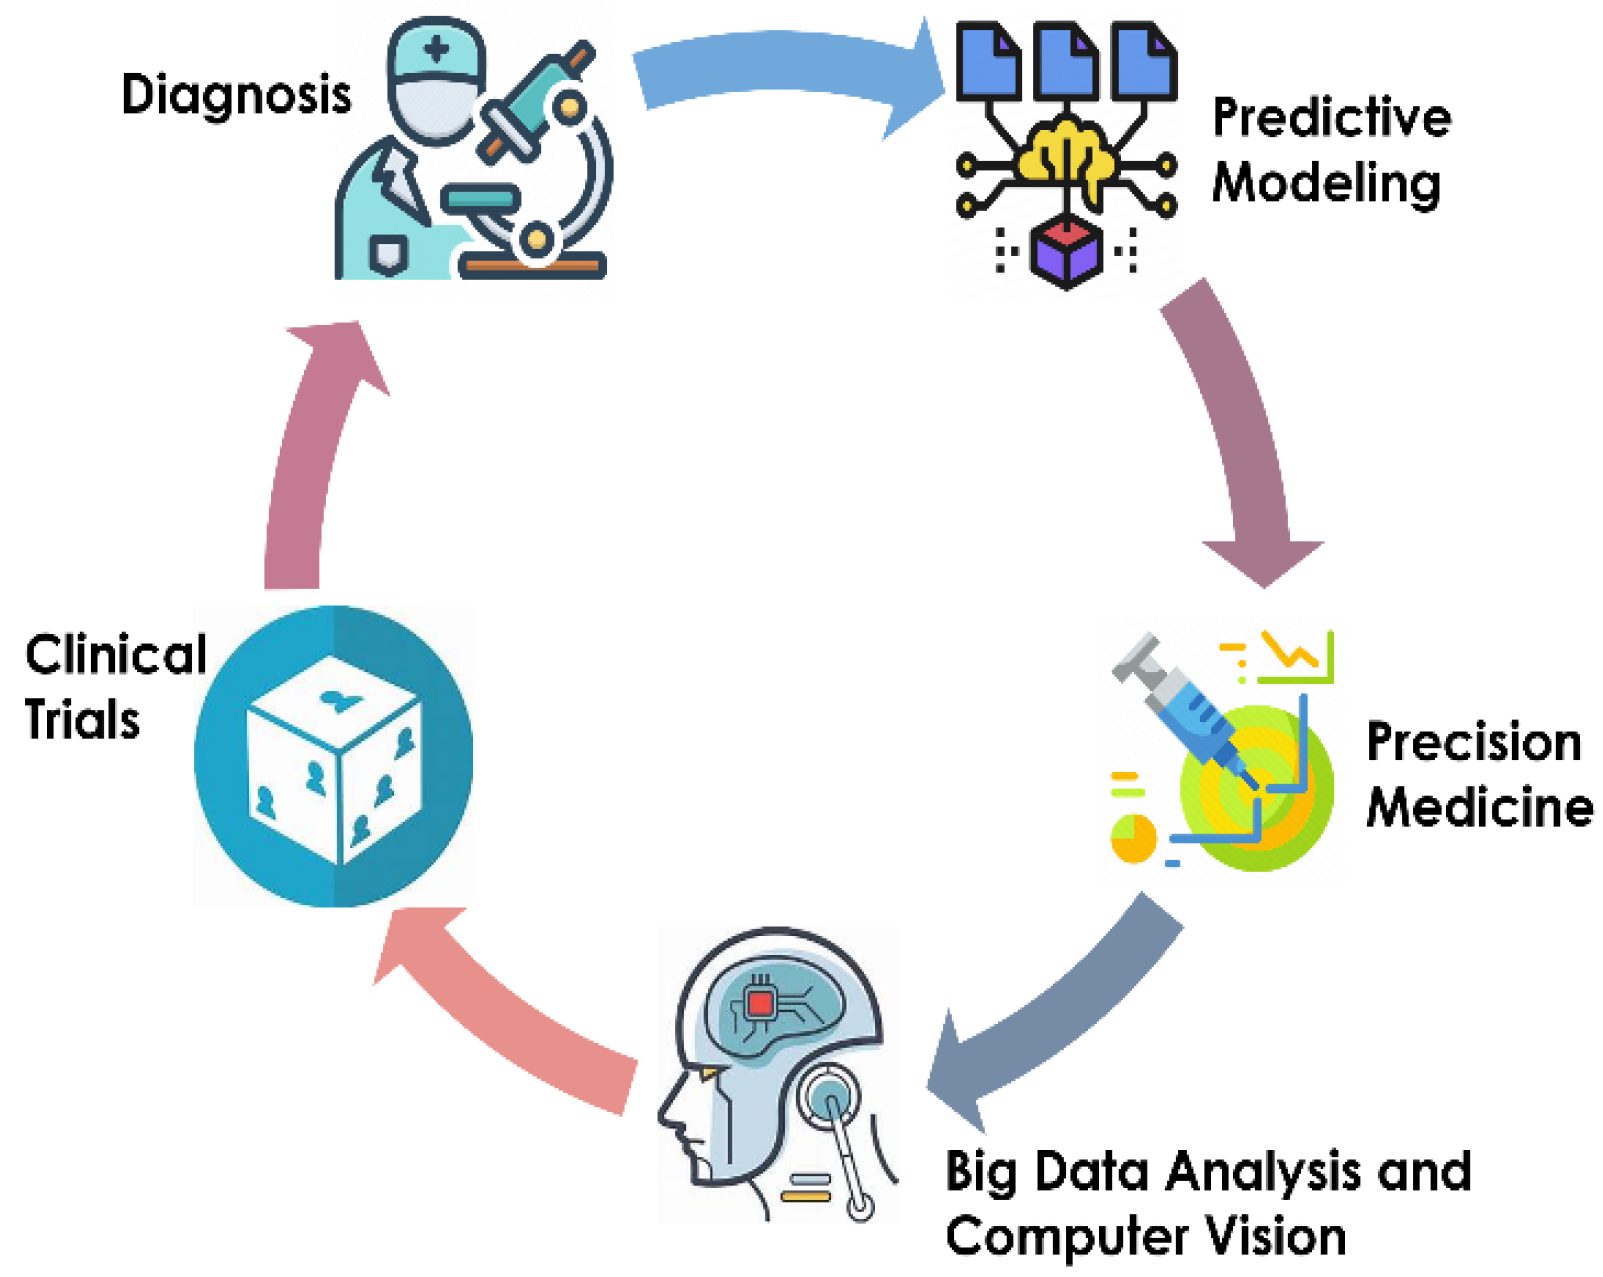

:1. Introduction

1.1. Background on Pediatric Urology

1.2. Importance of AI in Pediatric Urology

| Diagnosis | AI can aid in the accurate and early diagnosis of pediatric urological conditions through analysis of medical images and patient data [5]. |

| Treatment Planning | AI algorithms can assist in developing personalized treatment plans based on patient-specific factors, improving outcomes, and reducing risks [6]. |

| Surgical Assistance | AI-enabled surgical tools can enhance precision and safety during pediatric urological procedures, reducing complications and recovery times [7]. |

| Predictive Analytics | AI can help predict progression of certain urological conditions in pediatric patients, allowing for proactive intervention and management [3]. |

| Research and Innovation | AI facilitates the analysis of large datasets to identify trends, patterns, and novel insights, driving advances in pediatric urology [8]. |

| Education and Training | AI-powered simulations and virtual reality environments offer valuable educational resources for training pediatric urologists and residents [8]. |

| Patient Monitoring | AI-driven monitoring systems can continuously track pediatric urology patients, providing real-time alerts for any concerning developments [6]. |